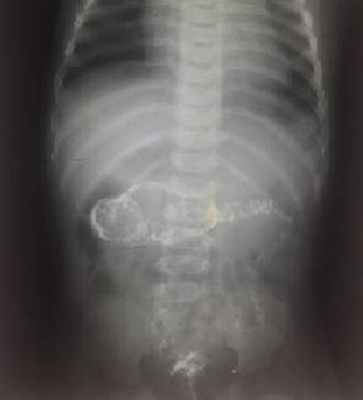

На рисунках 4 и 5 представлена картина кишечной инвагинации при рентгенологическом исследовании.

Рис. 4. Ирригограмма при тугом наполнении взвесью сульфата бария – симптом «клешней рака»

Рис. 5. Ирригограмма после опорожнения толстой кишки - симптом «кокарды»